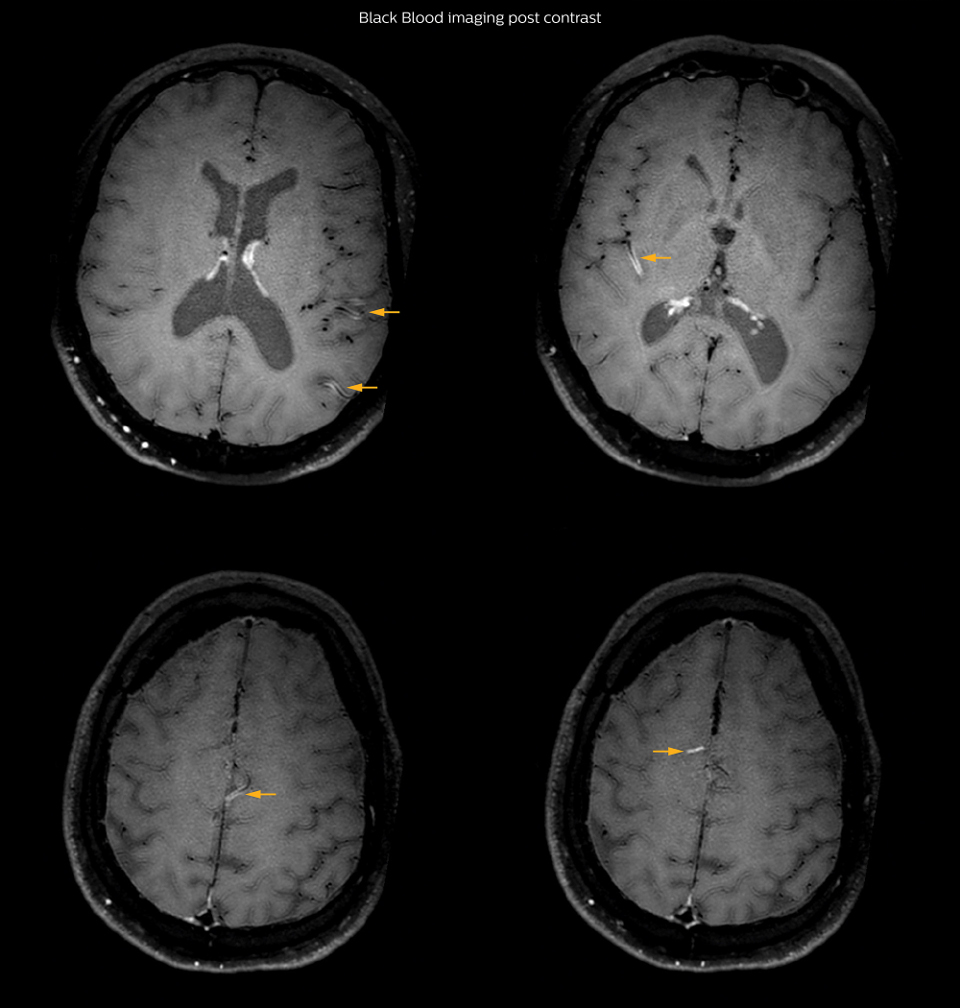

On FLAIR images we can see some nonspecific high signal abnormalities in frontal white matter bilaterally. On DWI we can see acute ischemic lesions which appear with high signal intensity. Arrows show vessel wall enhancement which appears concentric and homogeneous in different cerebral territories.

On the routine MR sequences that we did, we could see acute ischemic lesions. We see them very well on the diffusion images, where acute ischemic lesions usually appear with high signal intensity and restricted diffusion. However, the etiology of these lesions cannot be derived from these images. An area of restricted diffusion was seen in the anterior cerebral artery territory and we concluded it was an ischemic lesion. On MR angiography we can just see if there is stenosis or vessel occlusion, but it does not provide us information on the etiology of this kind of lesion. So, we decided to perform Black Blood imaging. The presence and the pattern of vessel wall enhancement on Black Blood imaging, can help us to determine the etiology of the lesion. differentiate vasculitis from other causes of vasculopathy, such as atherosclerosis, with a high specificity [1-3]. In an atherosclerotic lesion, vessel wall thickening and enhancement are usually eccentric, while in vasculitis the wall thickening and enhancement are usually concentric, homogenous, and in a long portion of the vessel. of patients whenever their treatment is installed in order to determine the efficacy of a particular treatment. In this case the Black Blood imaging helped us to suggest the diagnosis of HIV-related brain vasculitis.

had, such as glucose intolerance, arterial hypertension and hypocholesteremia, his lesions could be atherosclerotic lesions or vasculitis, conditions which require different treatment. Especially in this patient with HIV infection causing the vasculitis, treatment of the two conditions is different. The results of MRI with Black Blood imaging, helped to choose the preferred treatment for this patient, which was based on antiviral medication rather than an antiaggregant or anticoagulation treatment which is usually given to patients with risk of ischemia based on atherosclerotic lesions. One month after beginning the antiviral treatment, the same MRI examination was repeated and again 8 months after the beginning of treatment. On follow-up images, we see the enhancements have almost disappeared. So in case of this patient, the MRI exam with Black Blood imaging helped us to give the patient the appropriate treatment and also allowed us to noninvasively confirm the treatment response.

With the multiple cardiovascular risk factors this patient

After one month of treatment, post-contrast Black Blood images at the exact same levels as in the figure above show disappearance of the vessel wall enhancements which were seen on the previous examination.